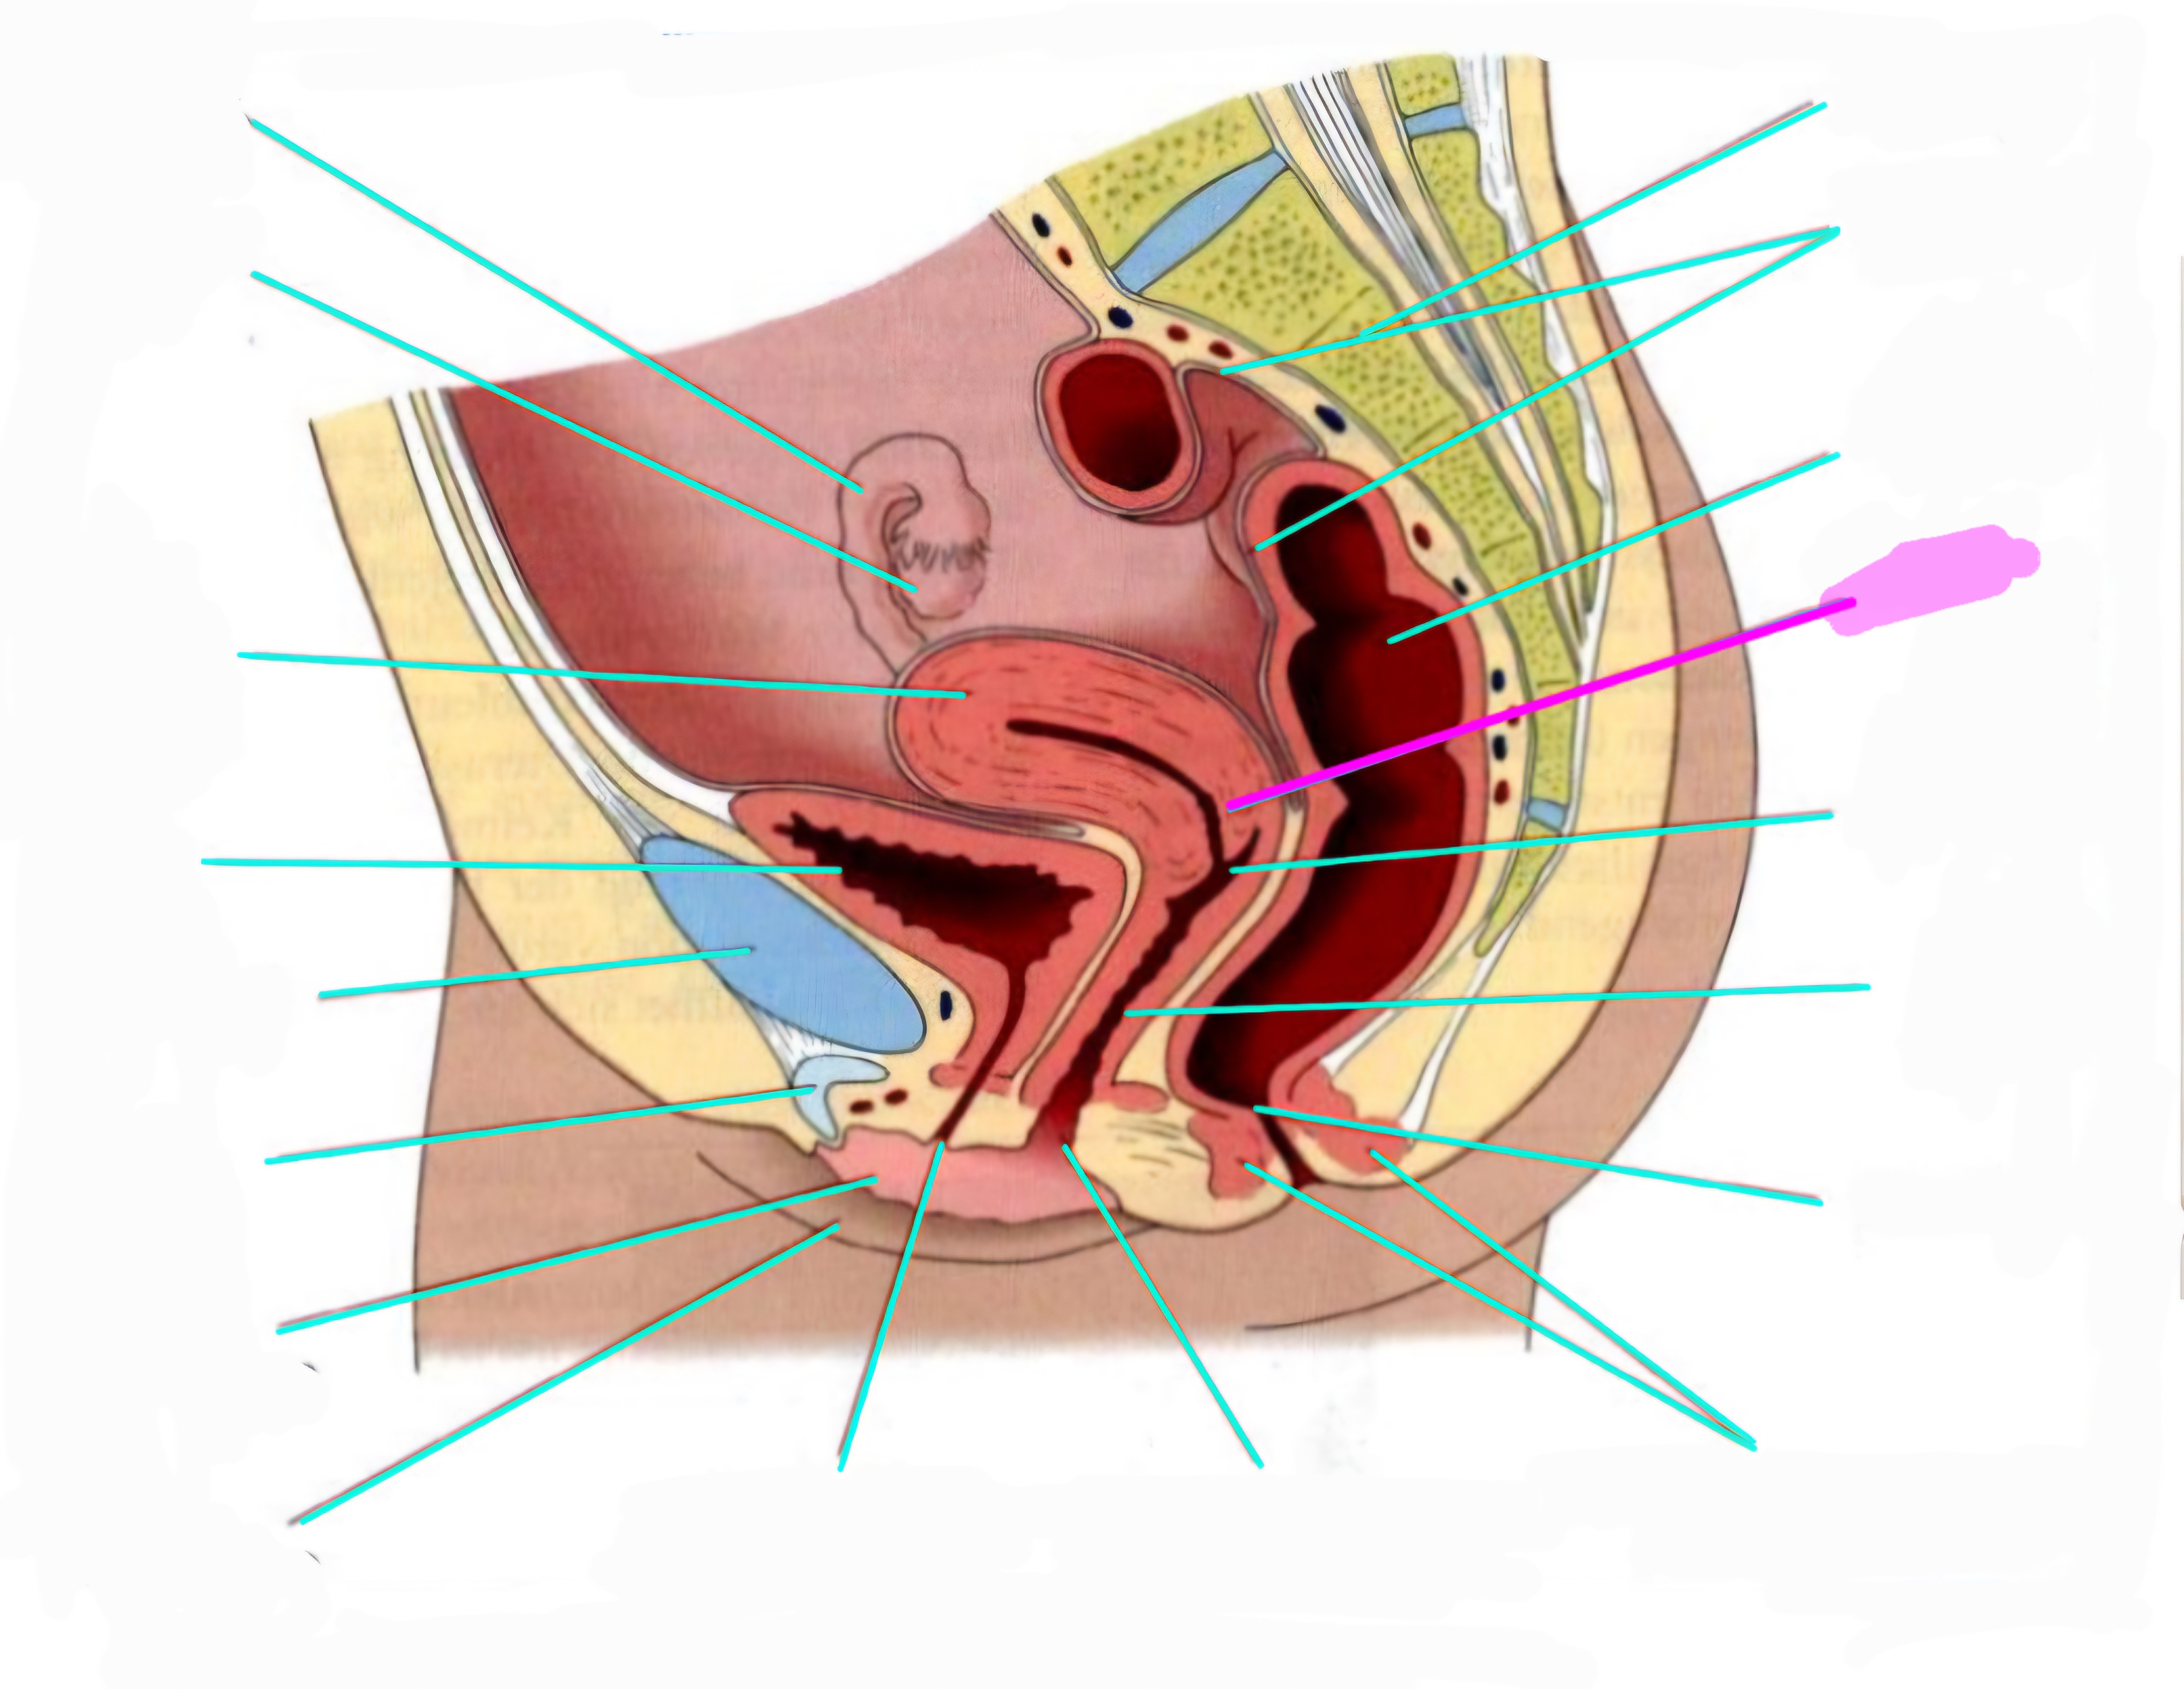

wbl. genital Anatomie

19 Terms

Tubea uterina (Eileiter)

Ovar (Eierstock)

Uterus (Gebärmutter)

Vesica Urinaria (Harnblase)

Symphyse

Klitoris

Labia minor pudendi (kleine schamlippen)

Labia Majoran pudendi (große Schamlippe)

Urethra (Harnröhre)

Introitus vaginae (Scheideneingang)

Sphincter ani externes (äußere Afterschließmuskel)

Anus (After)

Vagina (Scheide)

Portio (äußerer Muttermund)

Rektum (Mastdarm)

Zervix (Gebärmutterhals)

Peritoneum (Bauchfell)

Os sacrum (Kreuzbein)

Uterus: Topographie und Aufbau - wie groß ist er und wo liegt er?

7-8cm lang, Form einer umgedrehten Birne

Lage: im kleinen Becken zwischen Blase und Rektum

Antiversio: nach vorne geneigt, steht im Winkel zur Scheide

Antiflexio: in sich selbst geknickt, nach vorne abgebogen öber die Blase